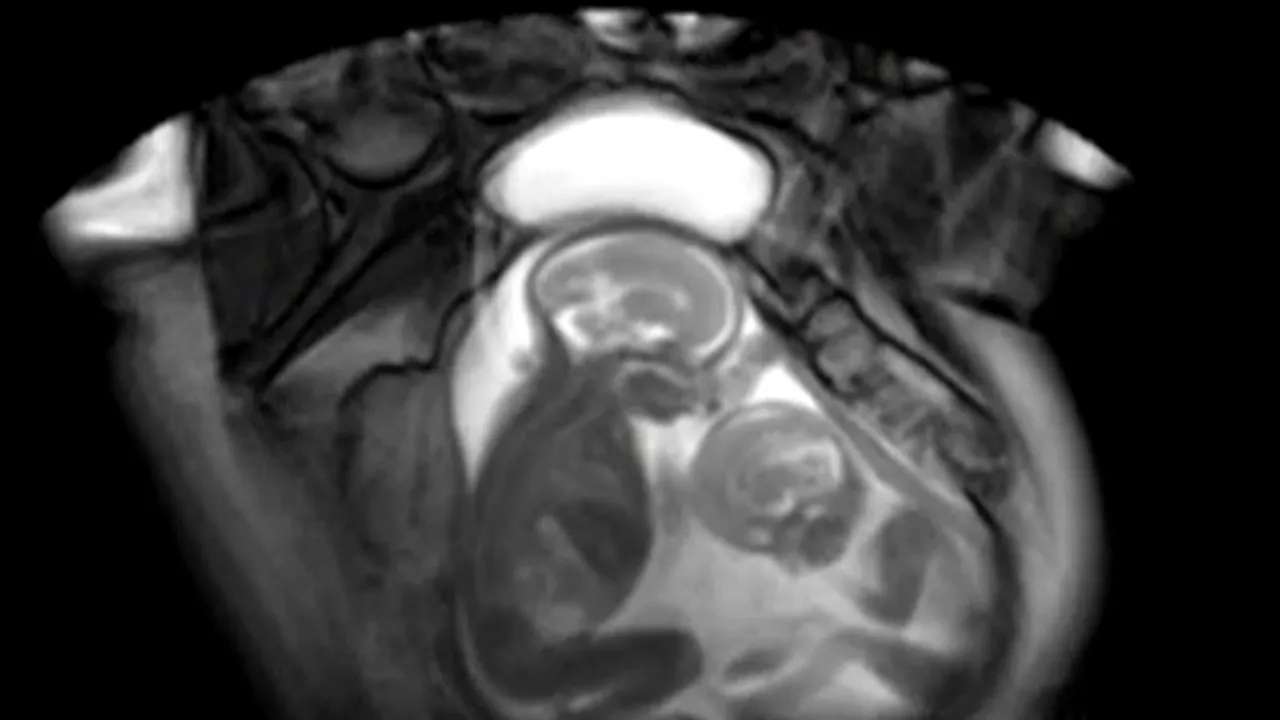

Cercetătorii britanici au realizat un RMN fetal din care reiese cum se „bate” o pereche gemeni pe spațiu, în pântecele mamei lor, scrie Huffington Post.

Din imaginile surprinse de specialiștii de la Imperial College din Londra, se observă că gemenii se mișcă și caută să ocupe cât mai mult spațiu în uter, schimbându-și des poziția.

Deși imaginile par amuzante, ele au un scop precis: de a stabili riscul ca feții să dezvolte sindromul transfuziei twin to twin (TTTS), adică situația în care unul dintre gemeni îi „donează” celuilalt sânge. TTTS face ca unul dintre gemeni să fie slăbit, din cauza lipsei nutrienților, în timp ce al doilea riscă să aibă inima suprasolicitată din cauza cantității mare de sânge.